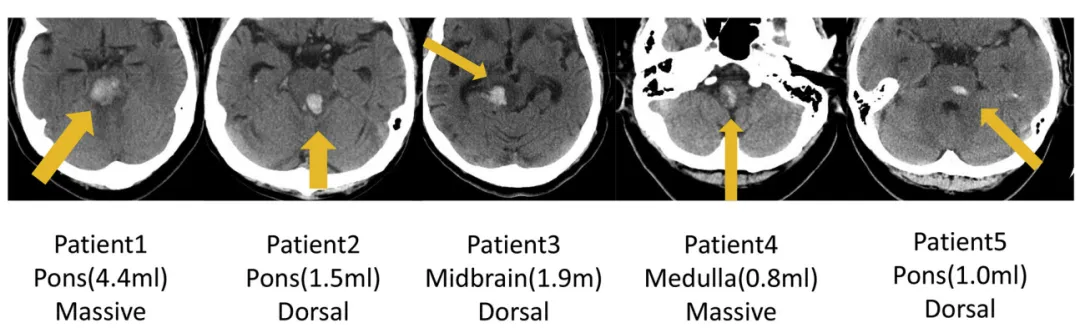

INC巴教授2018年發(fā)表論文《Surgical Treatment for Primary Brainstem Hemorrhage to Improve Postoperative Functional Outcomes》中討論了5例接受手術(shù)治療的原發(fā)性腦干出血患者,以及手術(shù)治療改善術(shù)后功能結(jié)果的能力,分析了術(shù)后1周的術(shù)后功能結(jié)果(表3)和出院后6個(gè)月的改良Rankin量表評(píng)分(表4),結(jié)果顯示均有所好轉(zhuǎn)。

圖:5例原發(fā)性腦干出血(PBH)患者的軸位CT影像。